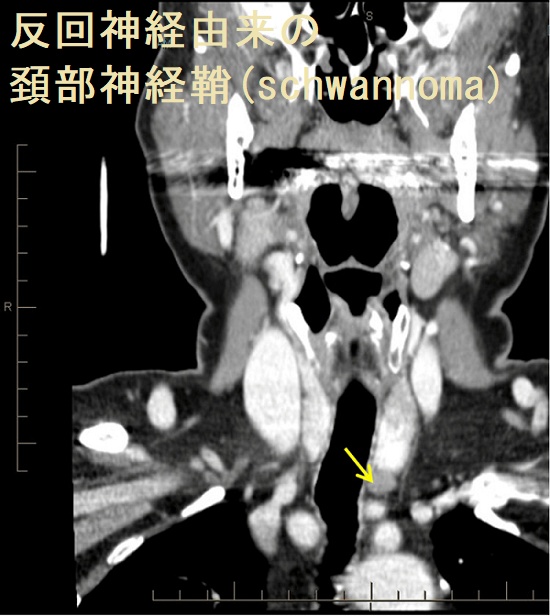

神経鞘腫は神経鞘中のSchwann細胞から発生する良性腫瘍で、25-50%は頭頸部領域に発症します(Cancer 24 : 355-366, 1969.)。頸部神経鞘腫の34%が迷走神経/反回神経、17%腕神経叢、16%頸神経由来です(頭頸部外科Mook No.2(斎藤等編).122~133頁,金原出版,東京,1986.)。

頚部神経鞘腫(schwannoma)は硬く、血流に乏しい腫瘤で、発生母体の神経(写真では迷走神経)に連続しています。

- 充実性、均一エコー型(solid pattern);エラストグラフィーでは硬い

- 不均一エコー型(multiple microcystic pattern)

- 辺縁増強を伴う嚢胞型(cystic pattern)

があります(耳鼻34:677 ~683 ,1988.)。